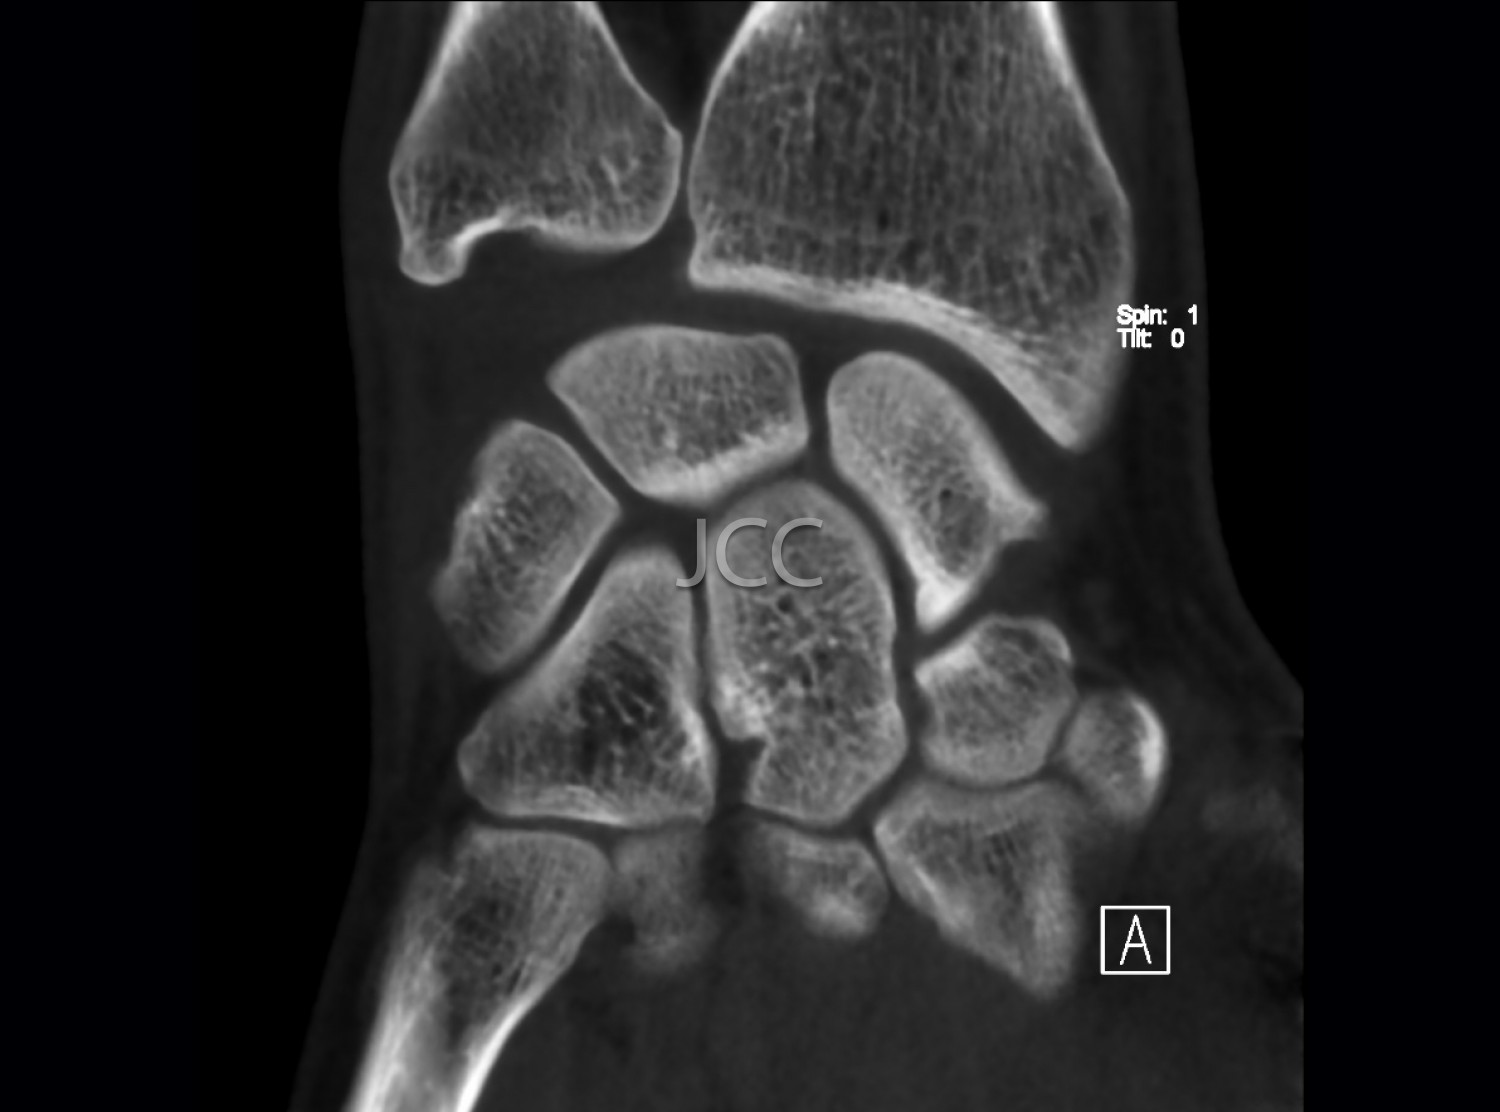

Cone Beam CT - Small Joints - Wrist / Hand / Fingers CBCT

We use a CBCT equipment which allows the study in low-dose radiation and very high spatial resolution of the bone structures of small joints, such as joints of the wrist, elbow, hands, feet, fingers, etc.

Taking into account the superior spatial resolution of the CBCT for bone evaluation compared to state of the art multi-cut CT equipment, this modality actually allows detecting small fractures or discrete small bone changes more effectively than the CT.

•Trauma to exclude small fractures

•Degenerative bone alterations